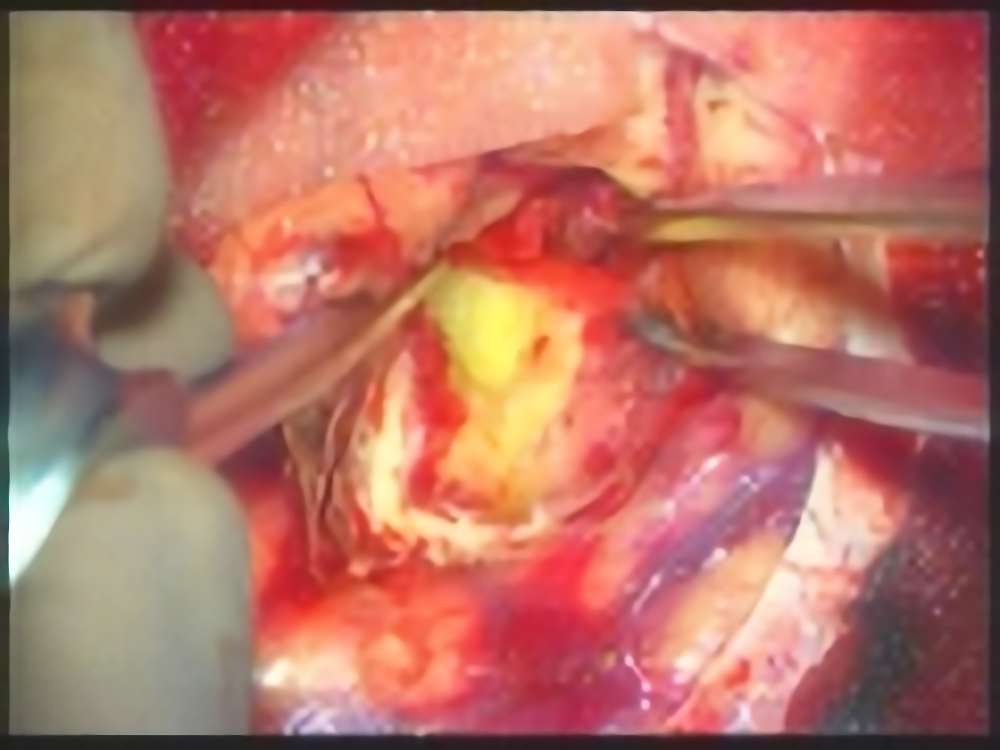

30代

海綿状血管腫

No.’15_49 手術前1

No.’15_49 摘出 前

No.’15_49 摘出 後